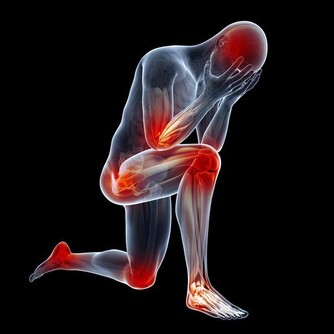

8. 非抗炎解熱鎮痛藥減緩背痛。

許多人會使用非抗炎解熱鎮痛藥來治療背部疼痛或關節炎,但這些藥物的效果其實非常有限,更重要的是,使用過多的話還可能導致肝臟出現問題。事實上,非類固醇消炎藥對於治療背痛還比較有效,但這種藥會有嚴重的副作用,也是無法長期服用。專家建議最有效的改善方法還是增強肌肉強度,但這需要時間。